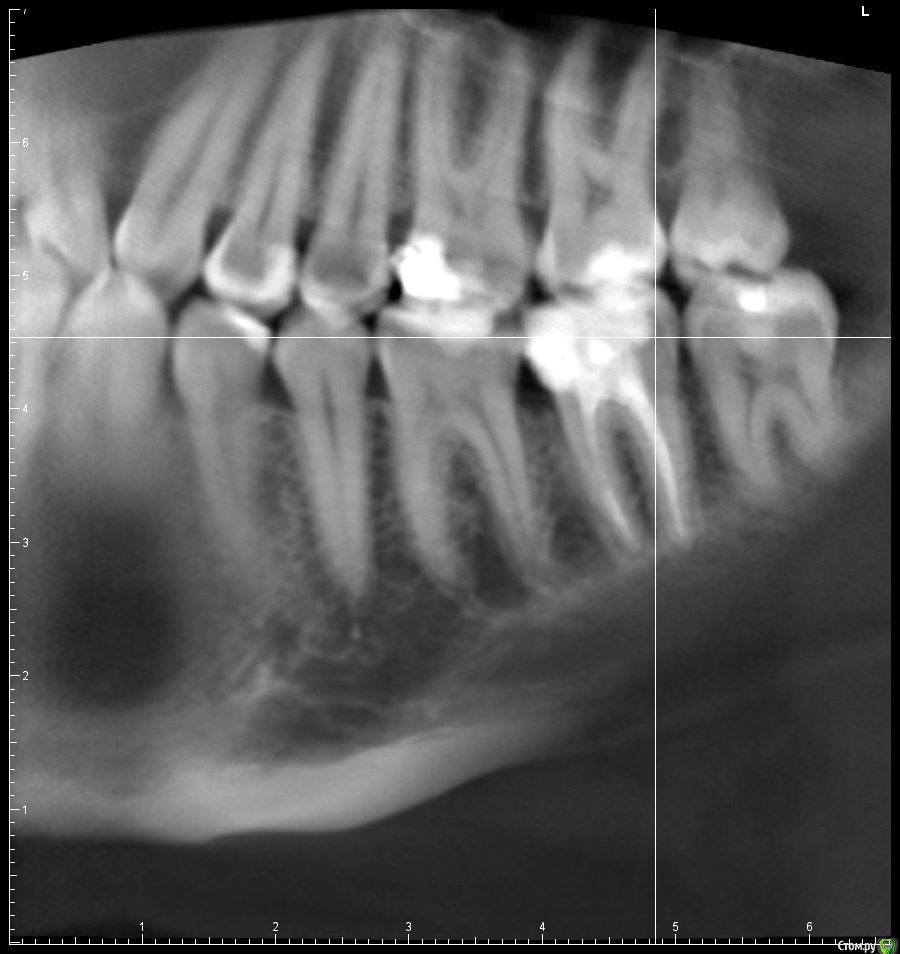

В августе прошлого года у меня начал сильно болеть десны и зуб на фоне обострения поллиноза. Врач обнаружил пульпит в болевшем зубе и еще несколько очагов кариеса по КТ. Очаги кариеса были запломбированы, в пульпитом 37 зубе было проведено депульпирование и пломбировка каналов. При пломбировке каналов врач что-то прижигал нагретой палочкой, раньше я думал, что при пломбировке использовалась гуттаперча. После лечения ощущались боли при надкусывании в 36 зубе несколько недель, на которые я не обращал внимания.

Прикладываю срезы с КТ от начала января 2017, скан распечатки прицельного снимка 36 37 зуба от ноября 2016.